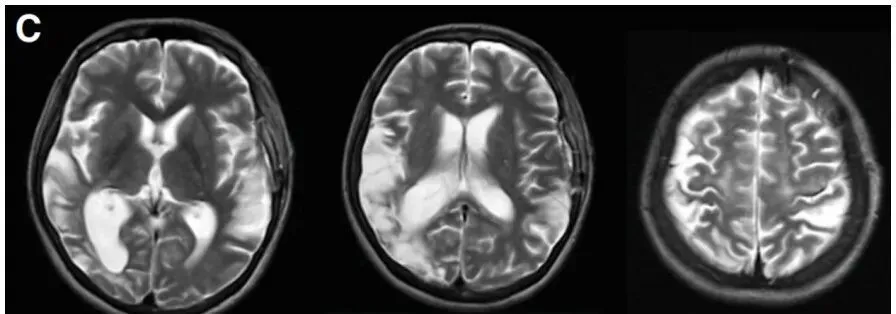

术前T2、DWI序列显示入院前1个月显示,既往右侧额顶叶脑梗死。

小玉的手术成功了,术后影像显示,左MCA区域的高血流灌注现象(图A),但未发生额外的缺血性和出血性并发症(图B,C)。无任何新发缺血或出血病灶。

术后20天血管造影显示,桥血管通畅,血流通畅;23天后的MR复查确认,未出现新的脑梗死或出血灶。